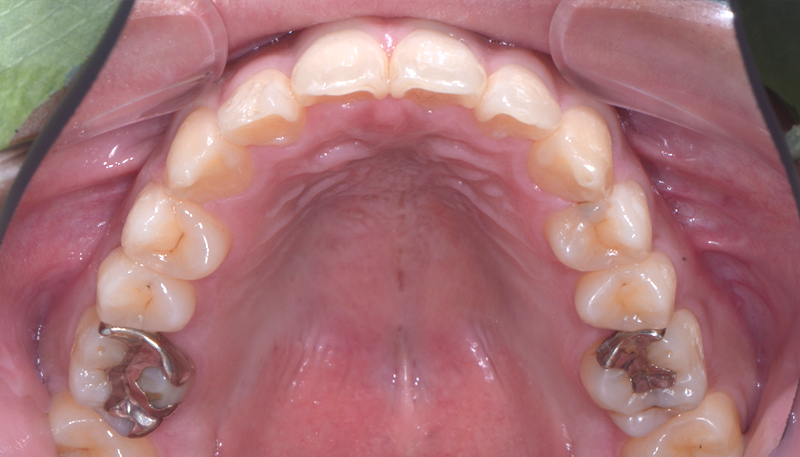

当院での矯正治療症例